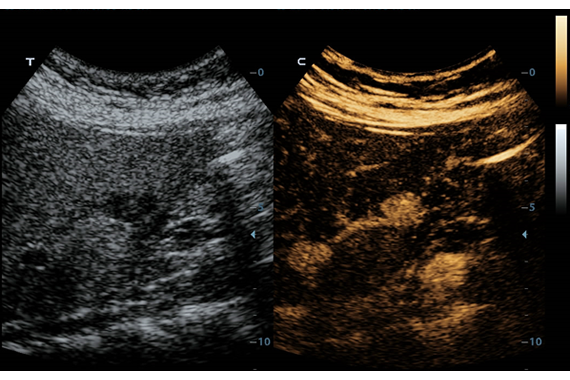

• HR Flow - режим отображения кровотока с высоким временным и пространственным разрешением для точной и однородной визуализации сосудов, в том числе самых мелких.

• UWN Contrast Imaging™ - опция для проведения обследования с применением контрастных веществ (поддерживается на датчиках L9-3E и P4-2)

• UWN Contrast Imaging™ QA - пакет для количественного анализа при проведении обследований с применением контрастных веществ (требуется установленная опция UWN Contrast Imaging)